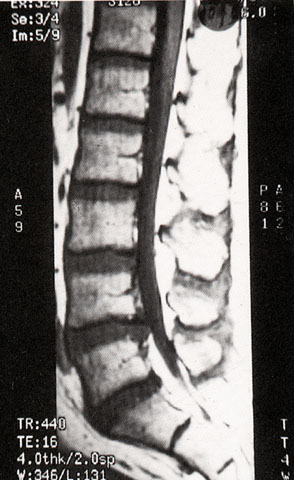

FH1073 椎间盘脱出(MRI)

图  名 椎间盘脱出(MRI)

导  学 阅图分析(与图1074、1075为同一患者)